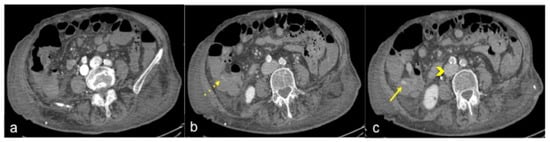

| Diverticulosis (Figure 33) | Asymptomatic or bleeding. | Protruding sacs where the vessels pass through the muscularis layer, between the mesenteric and antimesenteric taenia. |